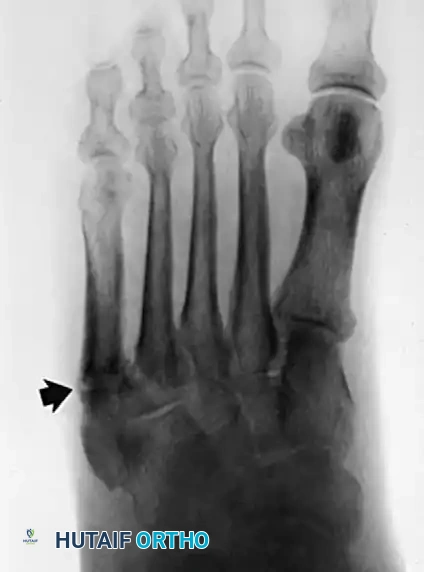

- Plain Radiographs: Weight-bearing anteroposterior, lateral, and mortise views of the ankle and foot are obtained to rule out fractures (e.g., "fleck sign" indicating SPR avulsion), os peroneum pathology, or varus hindfoot alignment.

Radiographic evaluation of the foot and lateral column.